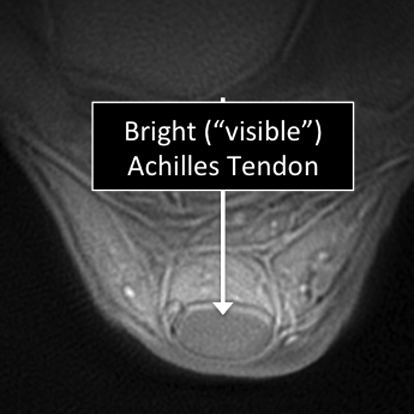

Ankle MRI examinations showing normal (top) and abnormal (bottom) Achilles tendon.

Why Translational MRI of the cartilage?

- Tendons are one of the several structures that can’t be seen (they look black or dark) with the standard MRI.

Ankle MRI examinations using the standard MRI techniques (top) and translational MRI techniques (bottom).